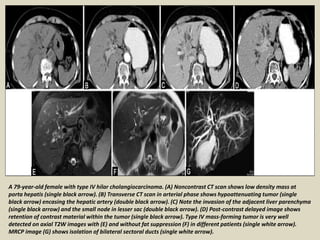

A 79-year-old female with type IV hilar cholangiocarcinoma. (A) Noncontrast CT scan shows low density mass at

porta hepatis (single black arrow). (B) Transverse CT scan in arterial phase shows hypoattenuating tumor (single

black arrow) encasing the hepatic artery (double black arrow). (C) Note the invasion of the adjacent liver parenchyma

(single black arrow) and the small node in lesser sac (double black arrow). (D) Post-contrast delayed image shows

retention of contrast material within the tumor (single black arrow). Type IV mass-forming tumor is very well

detected on axial T2W images with (E) and without fat suppression (F) in different patients (single white arrow).

MRCP image (G) shows isolation of bilateral sectoral ducts (single white arrow).